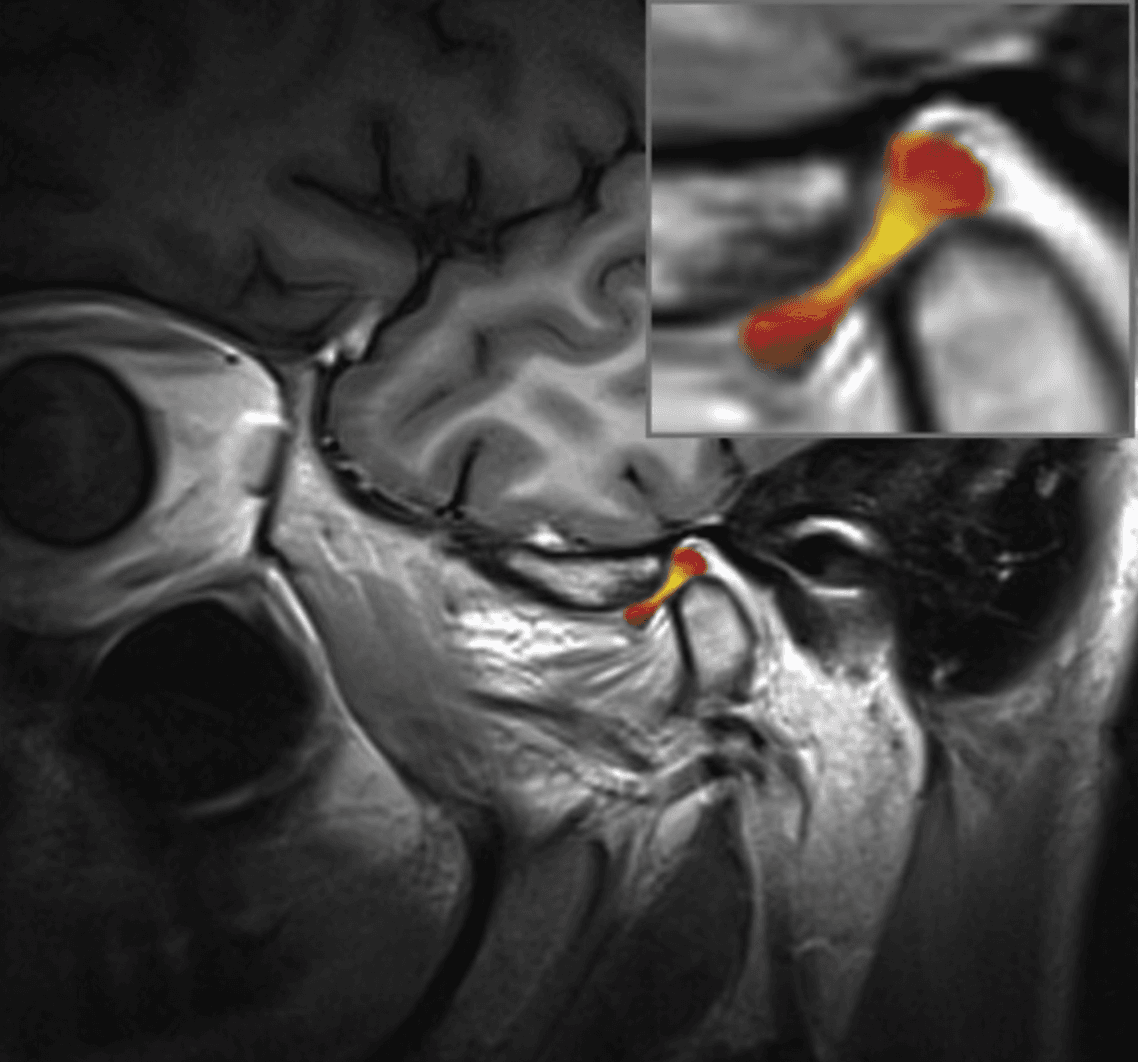

The oral and maxillofacial surgeon plays an important role in the treatment of temporomandibular disorders (TMDs), which are conditions affecting the temporomandibular joints and the muscles that control jaw movement. This can manifest as various symptoms ranging from orofacial pain, interference or limitation in opening, locking in a closed or open position, or clicking and popping of the joint. The oral and maxillofacial surgeon is trained to evaluate and diagnose TMDs using clinical examination techniques, medical imaging (such as X-rays, MRI, or CT scans), and sometimes specialized tests to assess the function of the temporomandibular joint.

However, some TMDs may require a surgical approach due to their nature or the significant impact they have on function. As a general rule, the surgeon tends to choose the minimally invasive approach that is most appropriate in the circumstances. This may involve a simple joint injection, camera surgery (arthroscopy; an approach that allows access and manipulation of the joint contents without having to open it), or in some cases, open surgery (arthrotomy). Drs. Poirier and Badri have expertise in these fields of practice through their experience and specialization.